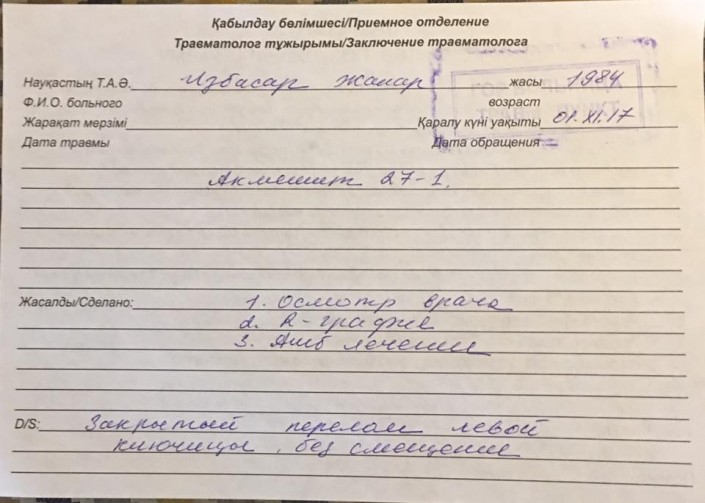

Ночью левая рука стала сильно болеть, обратилась в городскую больницу, рентген показал что у меня закрытый перелом левой ключицы, сейчас я мать четверых детей, гражданка Республики Казахстан стою перед фактом что органы и их сотрудники, которые должны защищать наши права, унизили и растоптали меня, морально и физически уничтожили, сломали мне ключицу, и скорее всего уйдут от ответственности, следователь ДГД сказал мне что решение примется через месяц, это я воспринимаю как "потянуть время", мы простые люди и не имеет высоких покровителей, надежда на общественность, которая может повлиять на этих сотрудников. Такое может произойти с каждым, помогите мне. P.S. на третьем этаже стояли несколько видеокамер, надеюсь записи дойдут до суда!!!", - написала она (пунктуация и орфография в основном сохранены - прим.).

Там же Избасар выложила фотографию заключения травматолога и рентгеновский снимок сломанной ключицы.